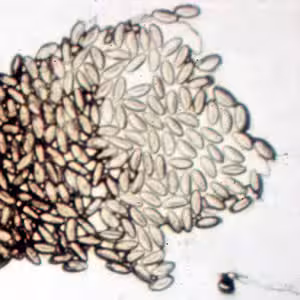

The eggs of Enterobius vermicularis measure 50—60 µm by 20—30 µm. They are transparent, elongate to oval in shape, and slightly flattened on one side. They are usually partially embryonated when shed. Enterobiasis can be diagnosed by applying cellulose tape to the anus of a suspect patient, especially in the morning before the patient’s first bowel movement. Eggs will adhere to the tape and can be seen microscopically.